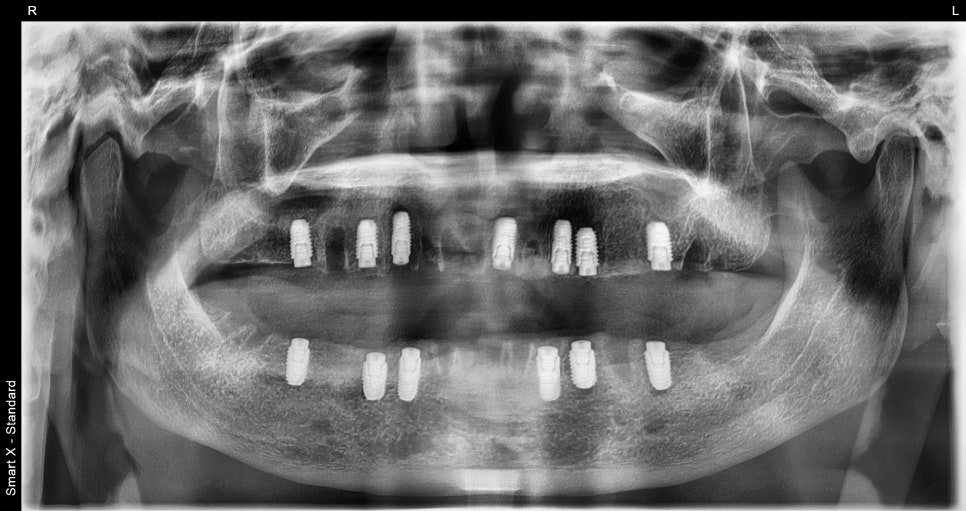

전악 수술은 발치, 골이식, 상악동거상술,

그리고 전체임플란트 13개 식립까지

모두 포함된 치료였으며

수면 상태에서 약 2시간 만에 완료되었습니다.

수술 과정에서 가장 중점적으로 본 부분은

어금니 임플란트의 위치와 각도입니다.

어금니는 전체 교합을 지탱하는 핵심 부위이기 때문에

저작력이 자연스럽게 분산되도록

정확한 깊이와 각도를 유지하며 수술을 진행했습니다.

장착 후 앞니와 어금니 모두 균형 있게 맞물리며

음식의 질감을 충분히 느낄 수 있는

교합으로 복원되었습니다.